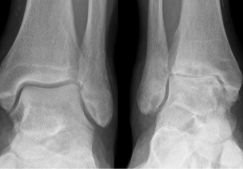

При подтверждении наличия патологии методами лучевой визуализации и отсутствии показаний к госпитализации пациенту нужно знать, как лечить артроз стопы в домашних условиях. Терапия занимает от 1 до 9 месяцев. Длительный срок объясняется непрерывным участием этого сегмента опорно-двигательного аппарата в активности человека на протяжении дня. Важно безошибочно определить, на какой стадии артроз стопы – лечение в домашних условиях приемлемо только при хроническом течении болезни или на раннем этапе ее развития.